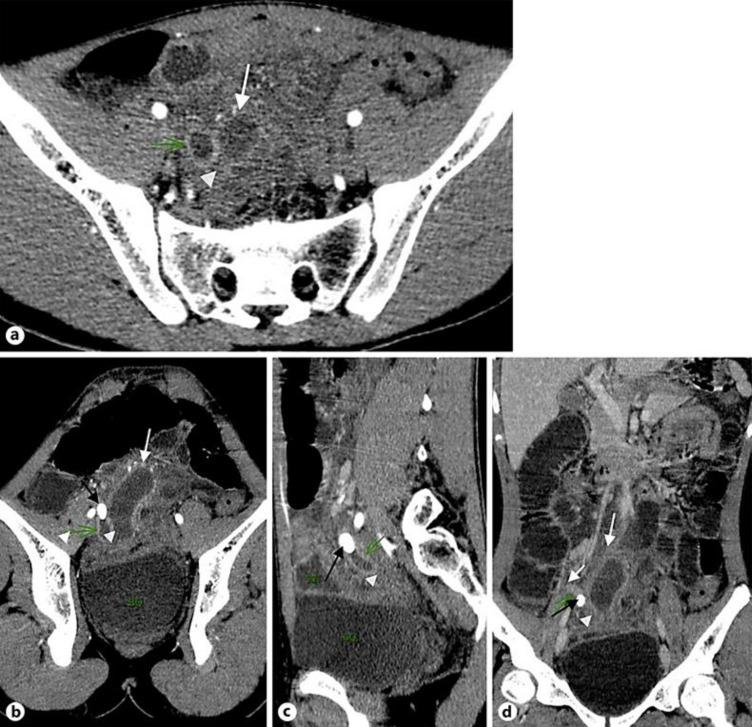

Acute appendicitis has been proven to be a usual cause of mechanical small bowel obstruction since 1901, but there has been very little specific research on this subject. It usually occurs as an effect of adhesion because of periappendicular inflammation. Although previous studies exist, this presentation of acute appendicitis is not widely identified, which might lead to delays in making the right diagnosis and initiating treatment. We herein report a 17-year-old male patient who presented with the clinical manifestations of intestinal obstruction and fever for 3 days. Preoperative ultrasound and subsequent computed tomography were performed. On laparotomy, an obstructed bowel was seen, and the appendix was recognized to be the cause. We herein report a case of intestinal obstruction due to acute appendicitis and present an overview of the literature.

自1901年以来,急性阑尾炎已被证实是机械性小肠梗阻的常见原因,但关于这一主题的具体研究很少。它通常是由于阑尾周围炎症导致粘连的结果。尽管此前已有相关研究,但急性阑尾炎的这种表现并未得到广泛认识,这可能导致诊断延误和治疗延迟。我们在此报告一名17岁男性患者,他出现肠梗阻和发热的临床表现达3天。术前进行了超声检查及随后的计算机断层扫描。剖腹手术时,发现一段肠管梗阻,阑尾被确认为病因。我们在此报告一例因急性阑尾炎导致肠梗阻的病例,并对相关文献进行综述。